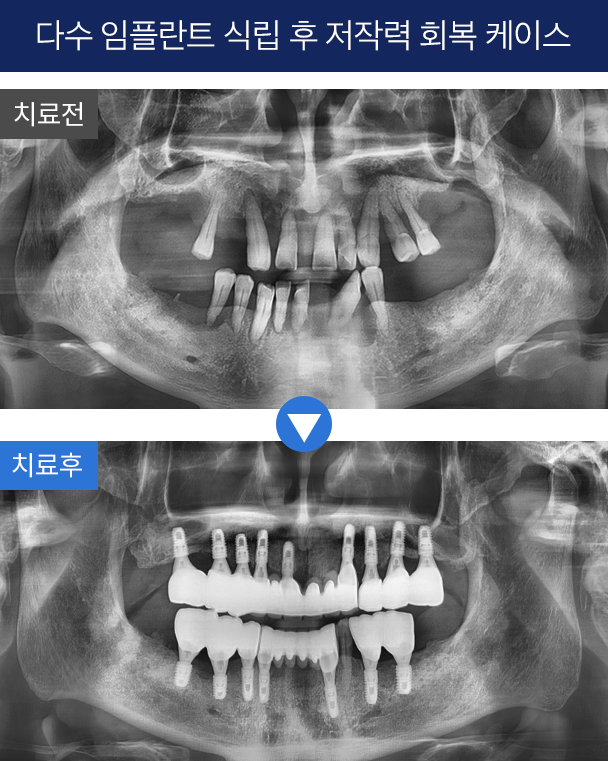

3